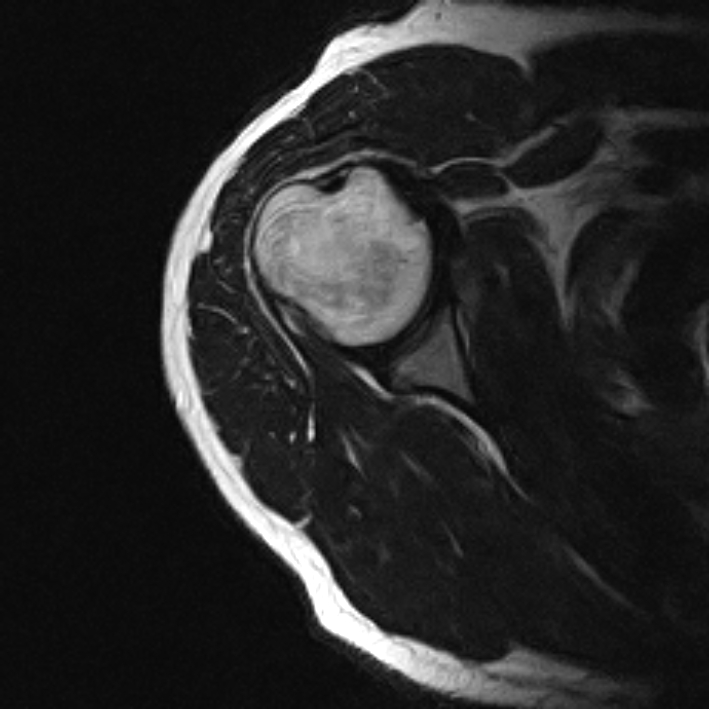

From www.indianradiology.com

Pitching InjuryMRI Shoulder Sumer's Radiology Blog Shoulder Injuries In Pitchers shoulder pathology can manifest as pain, diminished performance (velocity and accuracy), or a decrease in strength or range of motion. shoulder injuries in pitchers are an unfortunate reality of baseball, resulting in games lost, time spent on the injured list,. this review describes a range of shoulder injuries experienced by baseball pitchers. although throwing injuries in. Shoulder Injuries In Pitchers.